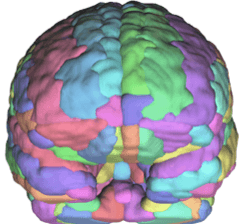

• Structural MRI analysis

• Volumetric analysis

• Morphometry

• Image registration/normalization

• Atlas based parcellation

Sample brain parcellation